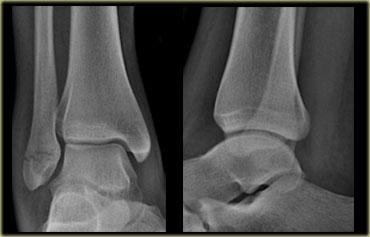

Các hình ảnh cho thấy gãy xương loại Weber A điển hình.

Tất cả đều là gãy xương giai đoạn 1.

Giai đoạn 2 cực kỳ hiếm gặp.

Chú ý hướng nằm ngang của các đường gãy.

Đây là các gãy xương kiểu giật đứt do kết quả của sự bong gân giật.

Stage 2

Giai đoạn 2 không phổ biến và dễ phát hiện.

Lực khép lớn hơn dẫn đến mắt cá trong bị đẩy ra theo chiều dọc hoặc chéo.

Giai đoạn 2 không vững vì vòng cổ chân bị gãy ở hai vị trí.

Lưu ý hướng nằm ngang của gãy mắt cá ngoài và hướng thẳng đứng của gãy mắt cá trong.

Những lực cực lớn hẳn đã đẩy bật mắt cá trong ra.